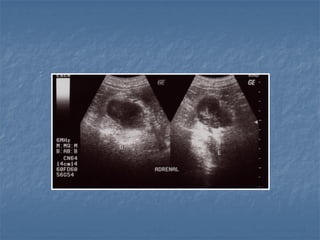

 Em gatos:

 glândula é mais curta, ovoide ou cilíndrica

(“grape tomatoes”)

 hipoecoica (cortical e medular distinguíveis)

 Podem ocorrer mineralizações em gatos

idosos (associada a hipertireoidismo)

 Em gatos: glândula é mais curta, ovoide ou cilíndrica (“grape tomatoes”)  hipoecoica (cortical e medular distinguíveis)  Podem ocorrer mineralizações em gatos idosos (associada a hipertireoidismo)  Estresse pode causar “white coat effect”  Gatos nefropatas crônicos apresentam adrenais em formato de bola de golf!

 Dimensões (gatos): 1,04± 0,18cm de comprimento 0,36 ± 0,07cm altura margem caudal (Combes et al., 2013)